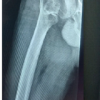

This case series includes four patients with an average age of 49.5 years (35–70 years), two women and two men, referred to the Orthopedic Surgery Department of the San Ignacio University Hospital at the Pontificia Universidad Javeriana of Bogota. Two of them with a history of oncological disease (proximal femoral chondrosarcoma and inguino-vulvar myofibroblastic sarcoma), assessed in conjunction with the oncological orthopedic service, ruling out a tumor relapse through local images and extension exams; another patient with a history of firearm injury to the left thigh with multiple secondary complications, which required various reconstructive procedures; and the oldest patient with a history of total hip replacement. The main complaint of the four patients was pain not caused by trauma, and none presented fever or associated systemic inflammatory response symptoms. Initial assessment radiographs of all patients showed signs of loosening of the prosthetic material and with microbiological cultures were established, septic etiology of the loosening in two of the patients and aseptic etiology in the other two patients (Fig. 1). Septic loosening was treated by a two-stage joint revision, once the patient showed no clinical signs of infection, C-reactive protein and arthrocentesis where negative, que second stage was performed. As a preliminary study, an arthrocentesis was performed in the four patients and active periprosthetic joint infection was ruled out, so they were scheduled for revision surgery of prosthetic components.